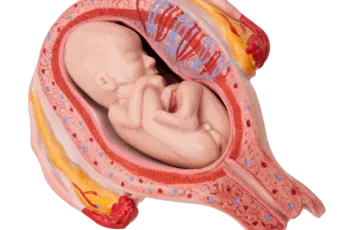

ניתוח קיסרי

ניתוח קיסרי -  המדריך עם כל המידע הרפואי והמעודכן לידה נרתיקית היא לידה "טבעית", שבה התינוק יוצא דרך תעלת הלידה (המחברת בין הרחם לנרתיק) באמצעות צירים שמכווצים את הרחם ודוחפים את התינוק למטה. לא תמיד אפשר ללדת בלידה נ